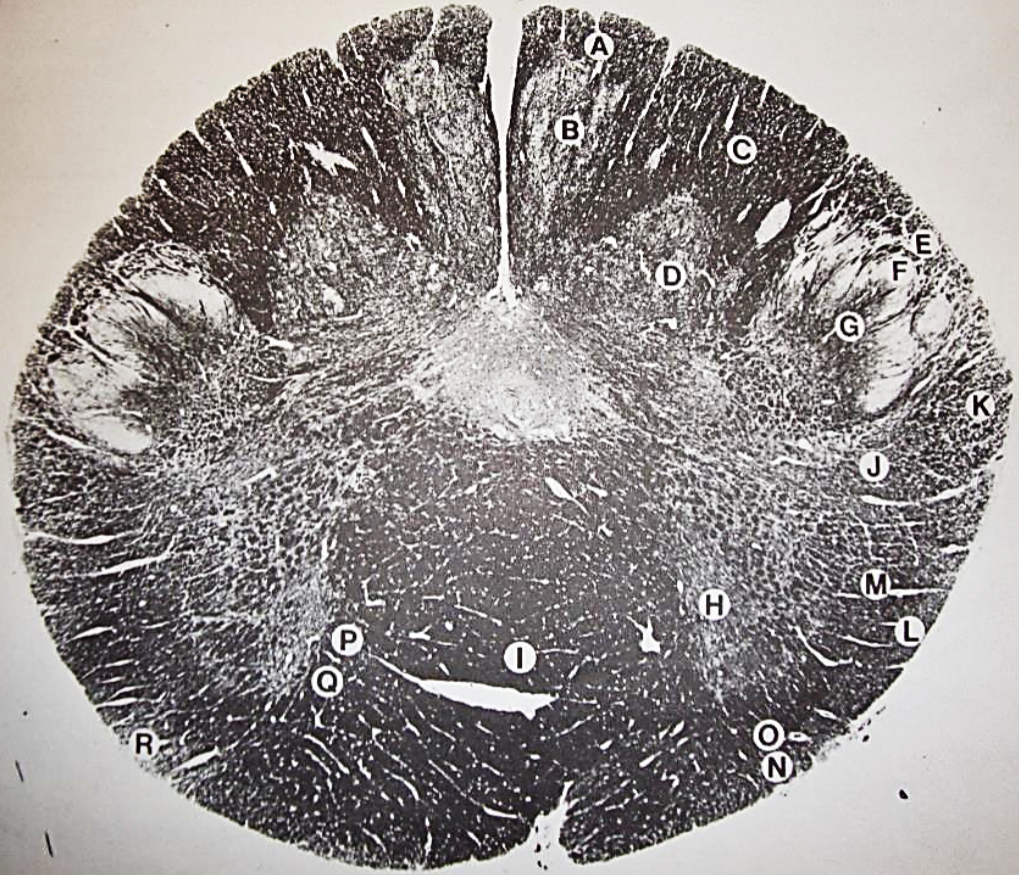

A

Lateral Cuneate nucleus

B

dorsal external arcuate fibers

C + D collectively

vestibular nuclei

C + D collectively

vestibular nuclei

E

dorsal motor nucleus of vagus nerve

F

solitary fasciculus

G

solitary nucleus

H

nucleus ambiguous

I

fascicles of glossopharyngeal nerve

J

hypoglossal nucleus

K

fascicles of hypoglossal nerve

L

dorsal longitudinal fasciculus

M

central tegmental tract

N

inferior olivary nucleus

R

inferior cerebellar peduncle

S

spinal trigeminal tract

T

spinal trigeminal nucleus

U

ventral trigeminothalamic tract

V

pyramidal (corticospinal) tract

W

rubrospinal tract

X

anterior spinocerebellar tract

Y

spinal lemniscus

Z

medial longitudinal fasciculus

a

tectospinal tract

b

medial lemniscus

c

vagus nerve

d

inferior salivatory nucleus